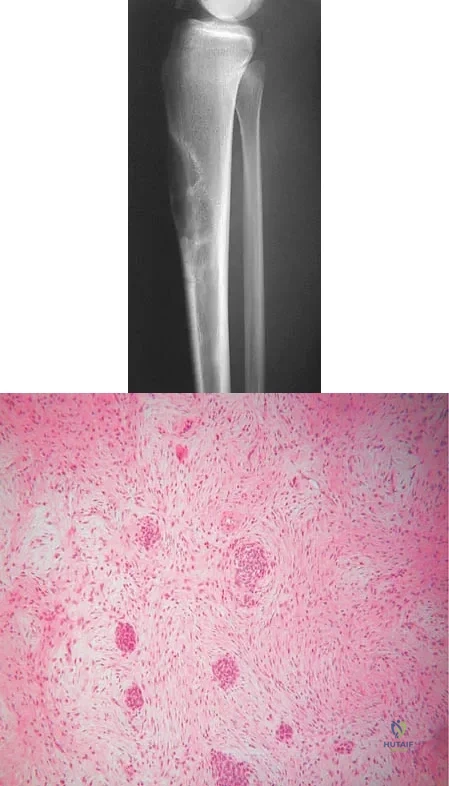

Question 16

A 16-year-old girl has had anterior leg pain and a mass for the past 8 months. Figures 2a and 2b show a radiograph and an H & E histologic specimen. Which of the following disorders is believed to be a precursor of this lesion?

Explanation